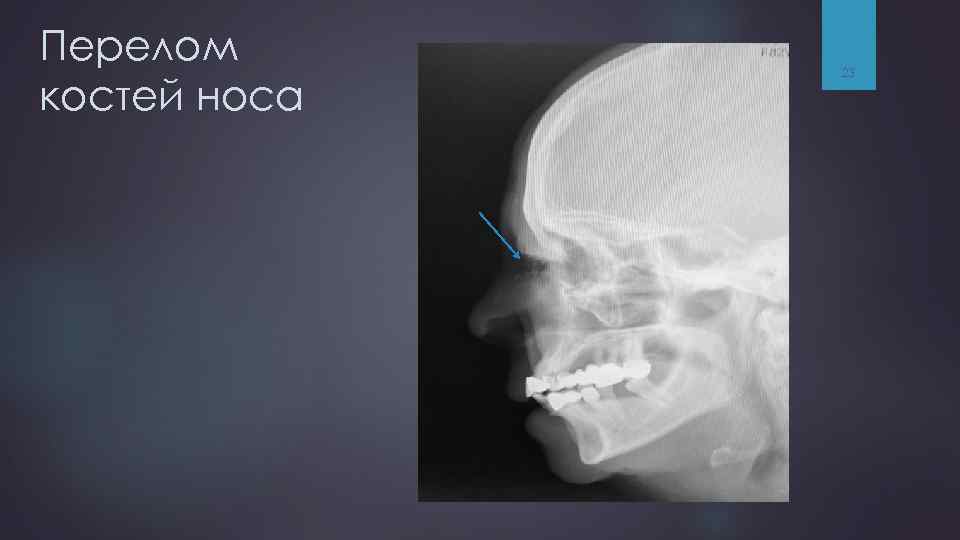

Перелом костей носа 23